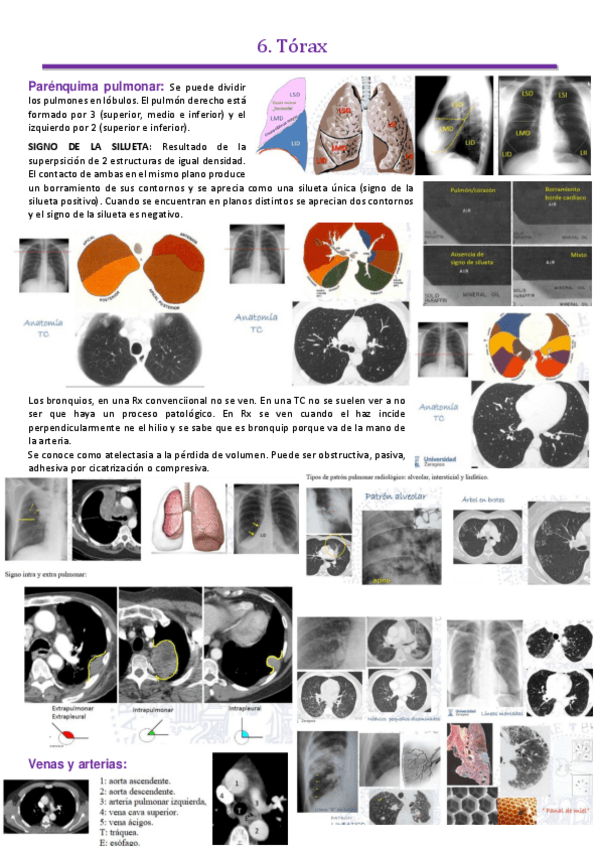

tema-4-torax.pdf